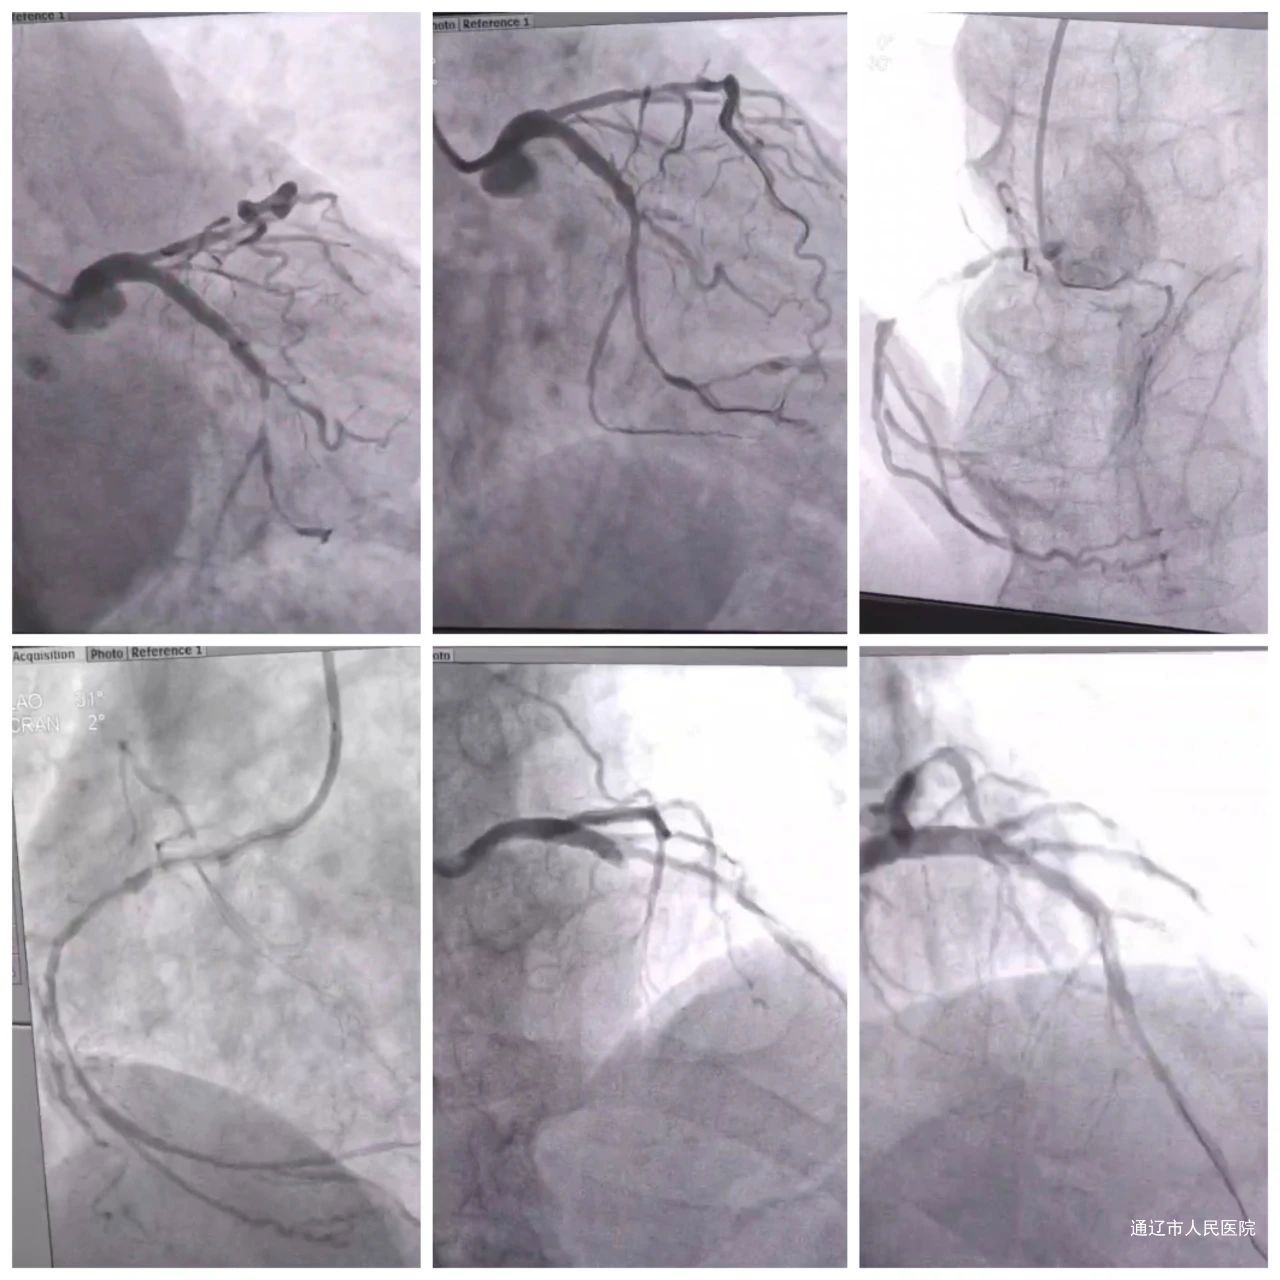

据统计,整个春节期间,胸痛中心累计接诊128名胸痛患者,其中急性心肌梗死患者达38名,30名患者成功接受急诊介入治疗。为有效应对春节期间胸痛患者数量增加,我院胸痛中心团队统筹谋划,对排班进行了科学调度和安排,全面充实和加强医护人员力量,各岗位全员实时上传交班时间管理表,全力保障生命通道的畅通无阻。

胸痛中心将“时间就是心肌,心肌就是生命”的理念落实到每一个救治环节。每一次对心肌梗死患者的精准、高效救治,背后都是胸痛中心团队的不懈坚守。以“时刻在线”的庄严承诺,守护着一方百姓的“心”健康。通辽市人民医院胸痛中心提醒广大市民:节日期间,饮食作息不规律,容易诱发心血管疾病。如出现胸痛、胸闷、气短等症状,请立即拨打120急救电话,并保持冷静,避免剧烈活动。通辽市人民医院胸痛中心,为您的健康保驾护航!